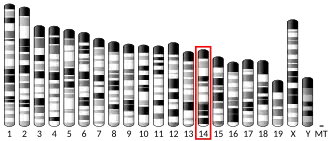

Urokinase is encoded in humans by the PLAU gene, which stands for "plasminogen activator, urokinase".[7] The same symbol represents the gene in other animal species.

- ^ a b c GRCh38: Ensembl release 89: ENSG00000122861 – Ensembl, May 2017

- ^ a b c GRCm38: Ensembl release 89: ENSMUSG00000021822 – Ensembl, May 2017